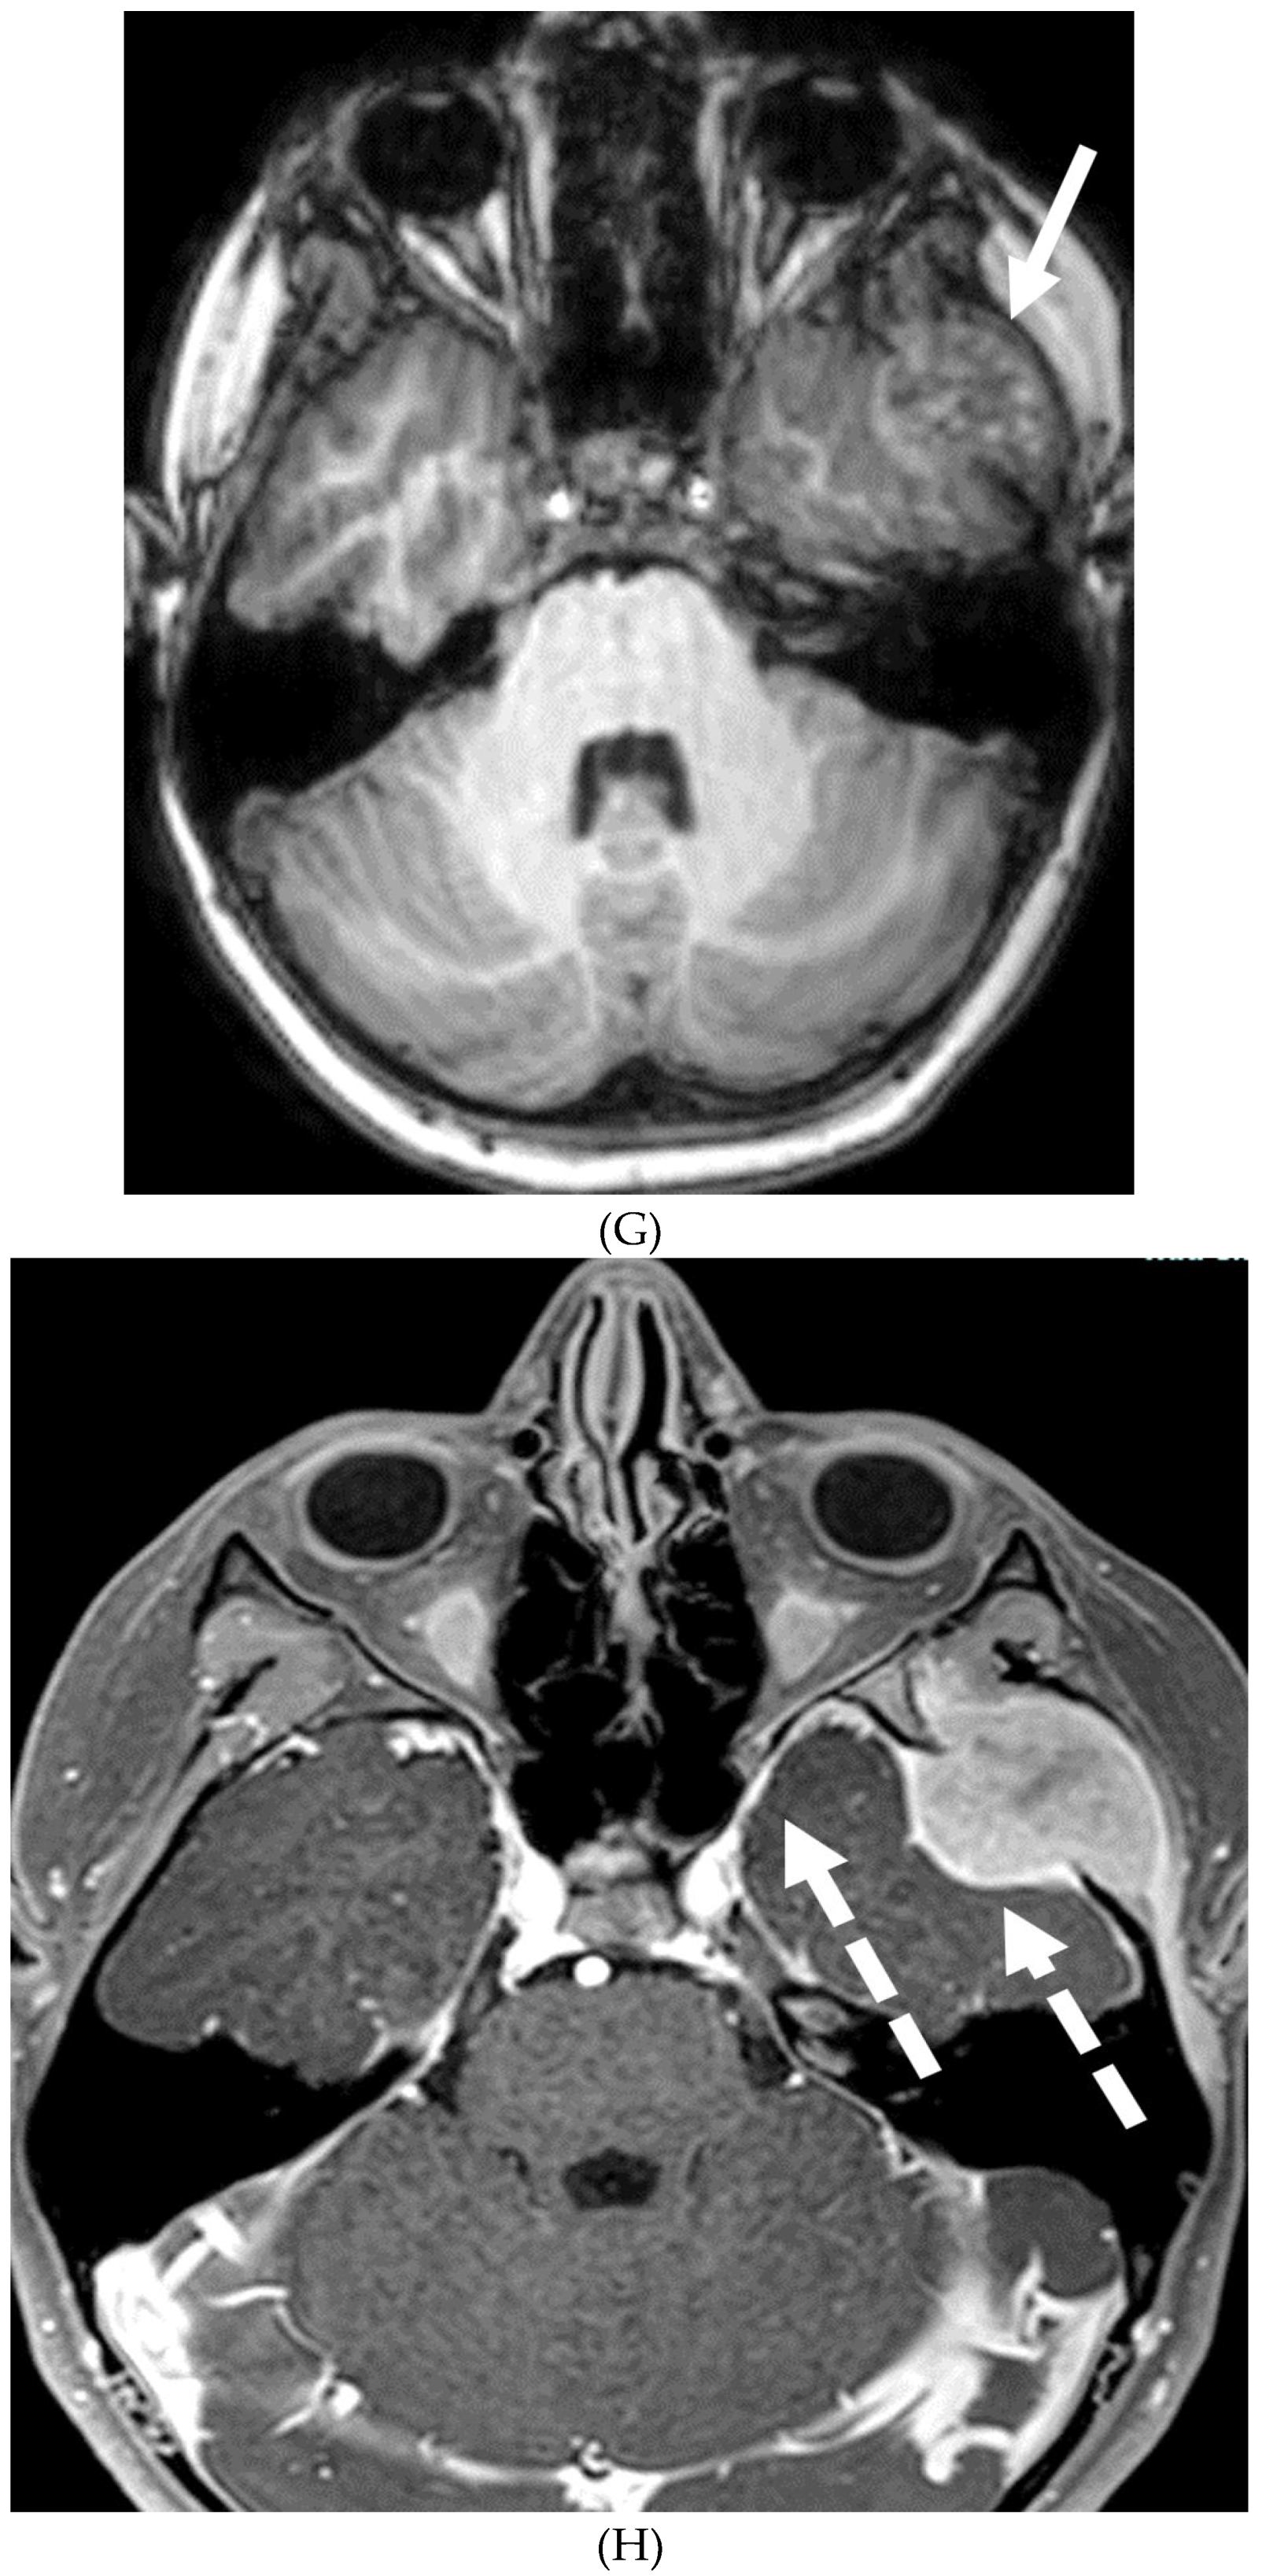

SYSTEMIC MENINGEAL METASTASES (SMM)

MOYA MOYA